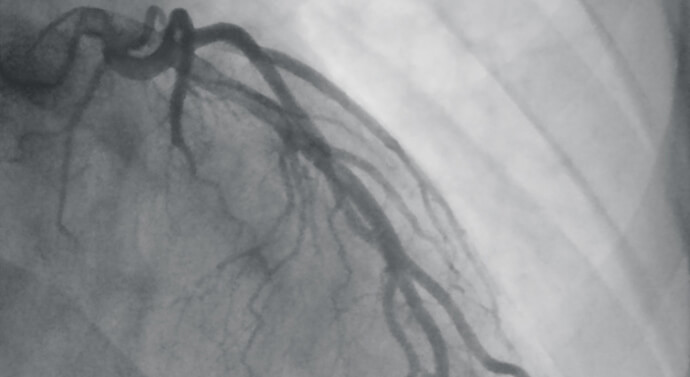

يمكن للقثطرة القلبية أن تفيد في عدد من الإجراءات التشخيصية والعلاجية، على سبيل المثال قد يحقن الطبيب عبر أنبوب القثطرة نوعاً خاصاً من الصباغ الذي يظهر على الصور الشعاعية، وبعد أن ينتشر هذا الصباغ في الدوران الدموي إلى القلب، تظهر الأوعية الدموية المغذية للقلب بشكل كامل؛ مما يعطي تصوراً عن حالتها الصحية، وهذا ما يدعى باسم تصوير الأوعية الإكليلية (Coronary Angiography).

- التصوير الوعائي (Angiogram): وتحديد أماكن التضيق أو الانسداد في الأوعية الدموية القلبية، يمكن أن يسبب هذا الانسداد ألماً صدرياً يدعى باسم خناق الصدر، أو احتشاء العضلة القلبية (أي تموّت النسيج العضلي القلبي بسبب عدم وصول كمية كافية من الدم إليه).

- توسيع الشرايين الإكليلية: الشرايين الإكليلية الوسيلة الأساسية لتروية عضلة القلب، لذلك يمكن أن يؤدي انسدادها أو تضيقها إلى موت الخلايا العضلية القلبية، وتتضمن عملية توسيع الشرايين الإكليلية إدخال أنبوب القثطرة القلبية إلى المنطقة المتضيقة من الشريان، ومن ثم نفخ بالون صغير ضمنه حتى يتوسع، كما يمكن بعد ذلك وضع دعامة معدنية تدعى باسم الشبكة (Stent) تسند جدار هذا الشريان المتضيق، وتحافظ عليه في حالة صحية قدر الإمكان.